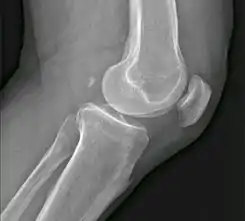

El fabela, también conocido como fabella, (del latín, pequeño frijol) (o flabelos) es un pequeño hueso sesamoideo se encuentra en algunos mamíferos incrustados en el tendón de la cabeza lateral del músculo gastrocnemio (gemelos) detrás del cóndilo lateral del fémur. Es una variante de la anatomía normal y presente en los seres humanos en 10% a 30% de los individuos. En raras ocasiones, hay 2 o 3 de estos huesos (fabela bi- o Tripartita). Puede ser confundido con un cuerpo suelto o de osteofitos. El fabela es un hallazgo normal en las radiografías del perro y el gato, y ambos medial y lateral fabellae son típicamente presentes.

![]() Fabela es la pequeña osificación en situación posterior de los cóndilo femorales. | ||